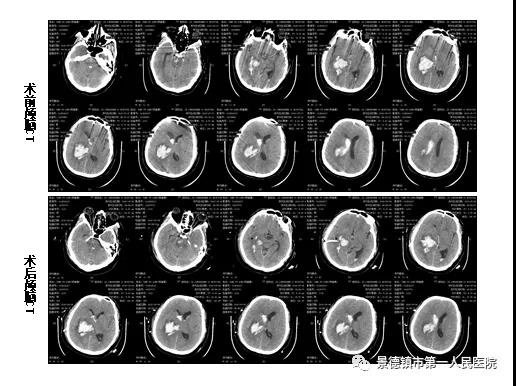

术后当即复查颅脑CT提示脑内血肿腔内引流管位置精确,正中靶心,脑室引流管摆放位置准确,引流通畅。

该患者经保守治疗6小时后,复查颅脑CT提示脑内血肿量无增大,故急诊在全麻下行立体定向软通道脑内血肿穿刺引流术+右侧脑室外引流术+颅内压探头植入术。术前潘长福医师通过微创立体定向治疗脑出血手术配套设备与患者头部CT图像相结合,实现脑内血肿三维立体定位,规划好穿刺路径及穿刺深度。

颅脑CT结果提示脑内血肿腔内引流管位置精确,正中靶心。